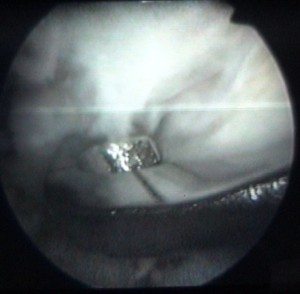

on voit la tête de la vis au milieu de la clé plate |

et le corps de la vis en-dessous |

cette vis sert à attacher le ligament |

et elle est maintenant vissée à fond |